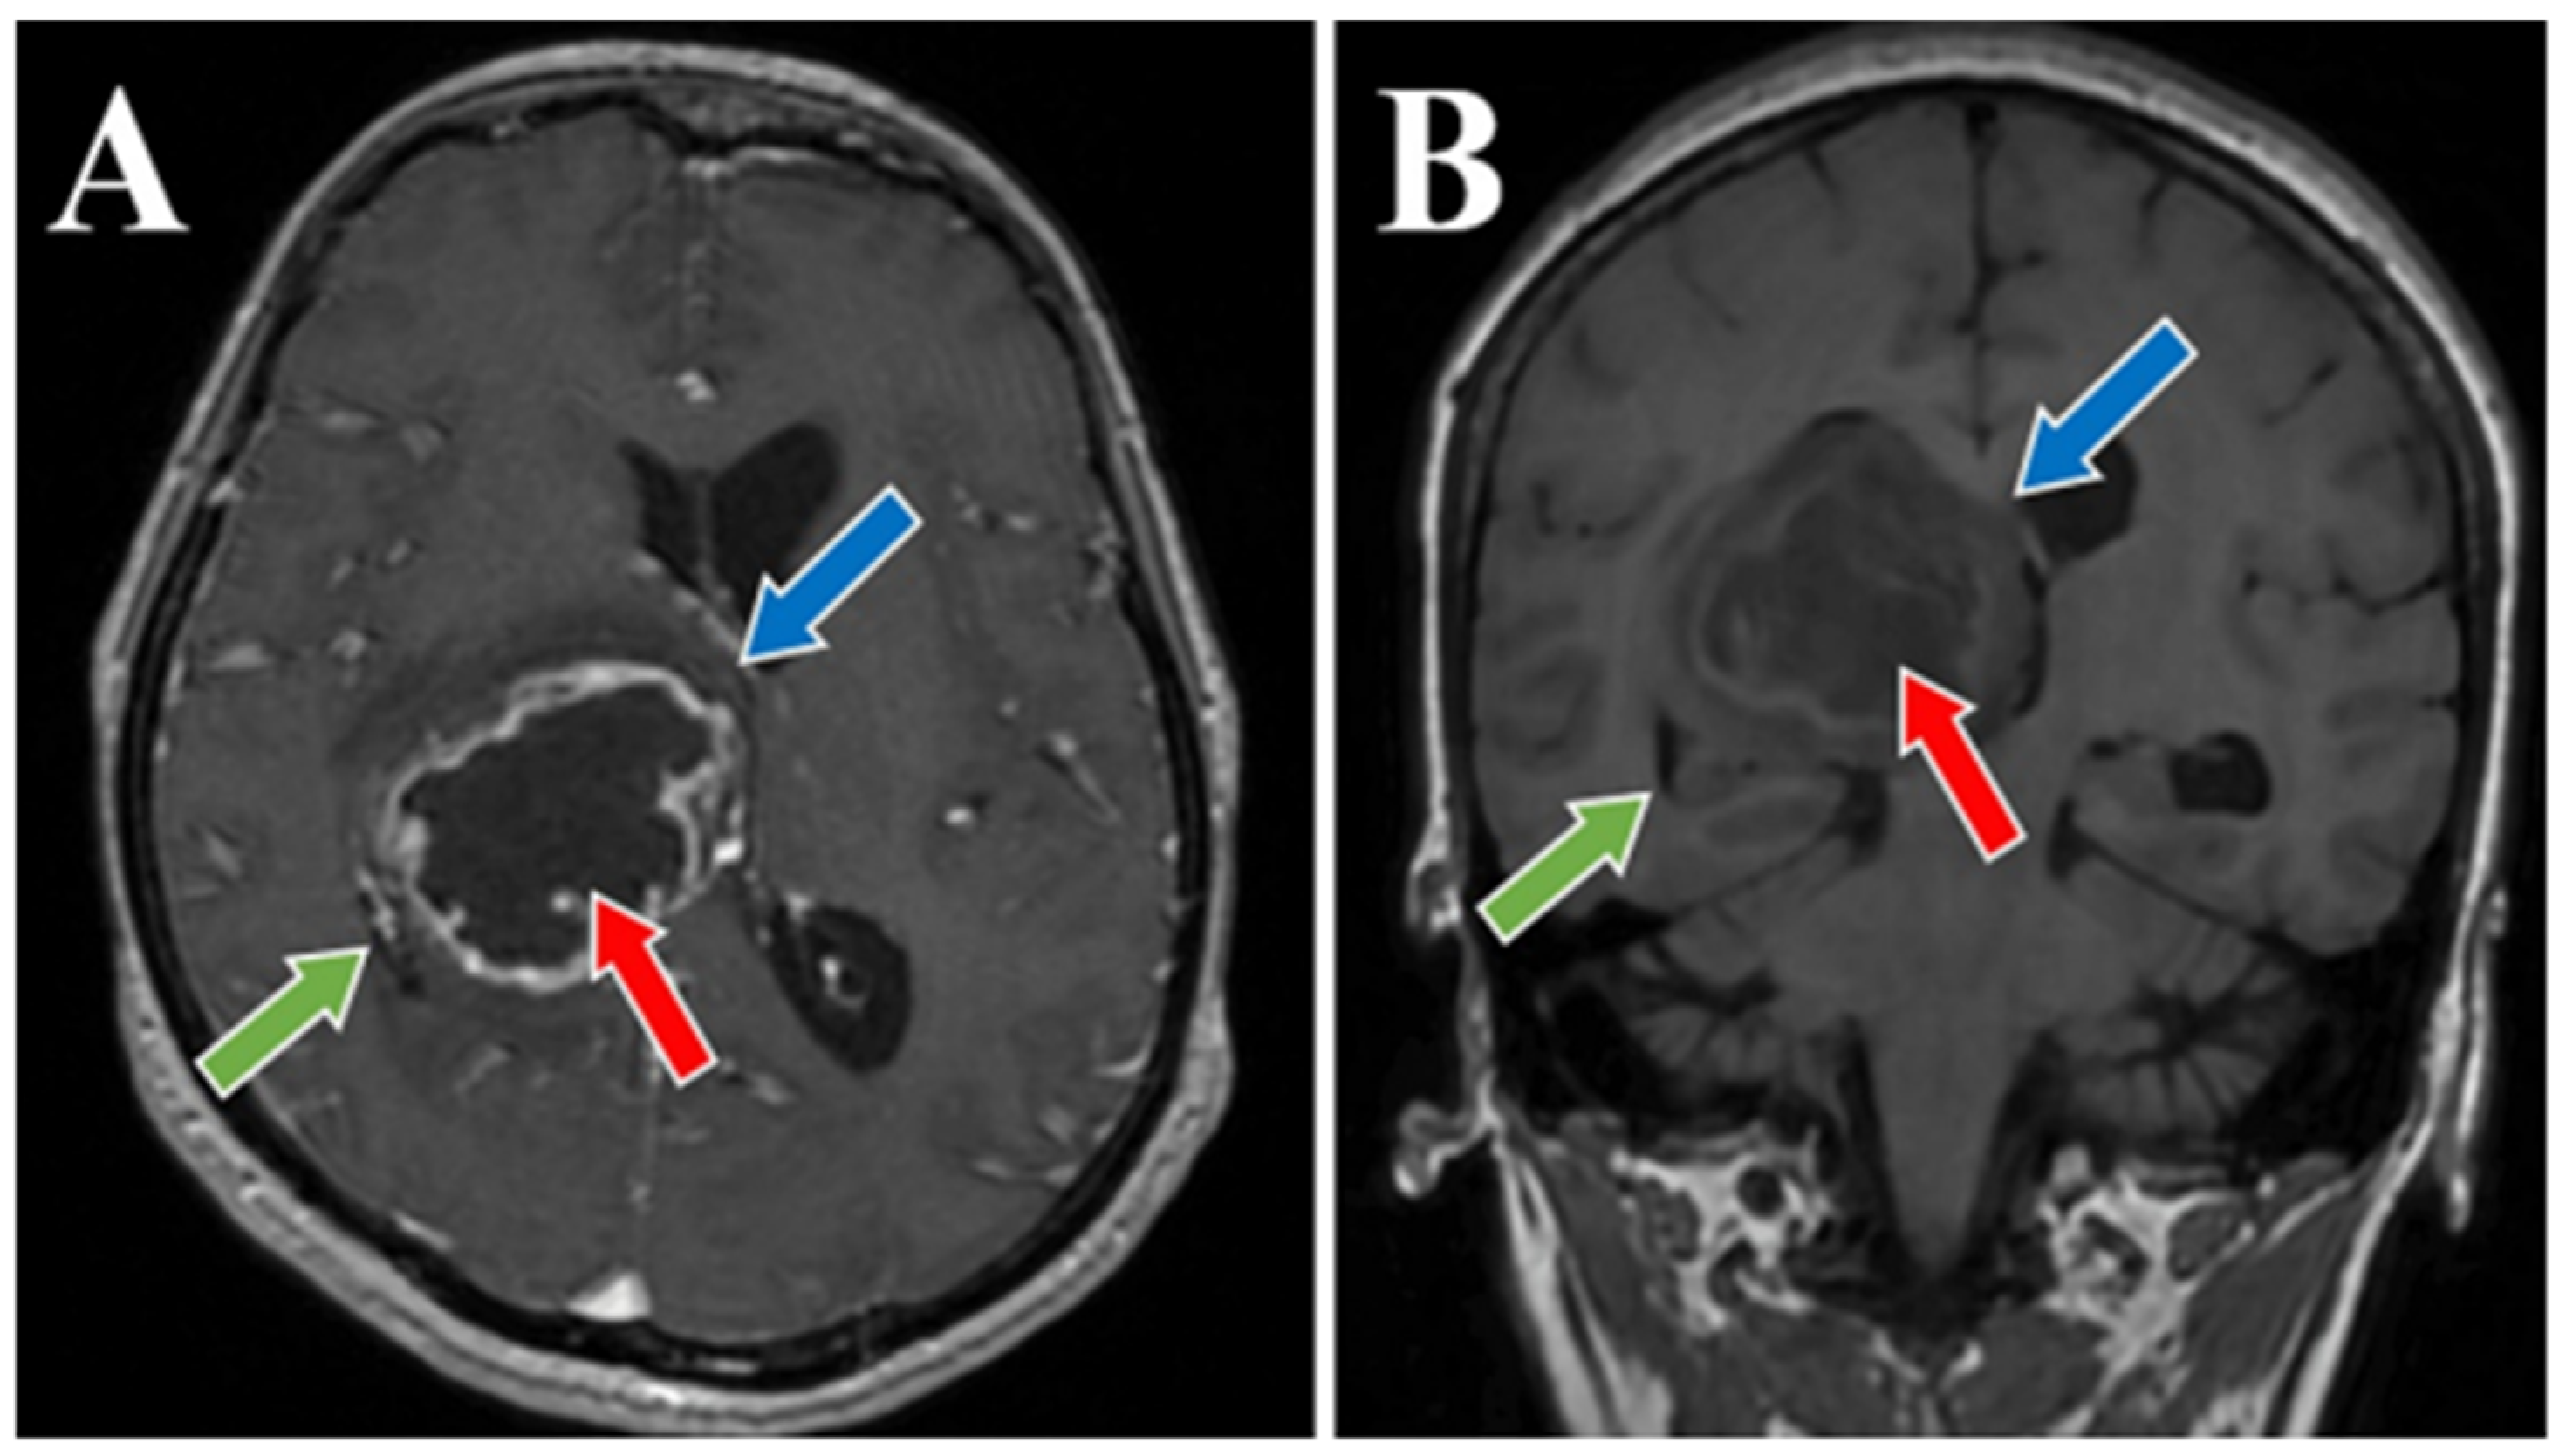

Figure 1. Preoperative MRI T1 and T1 Gd sequence, axial and coronal section. MRI T1 Gd-sequence axial section (A) and MRI T1 coronal section (B) both depict a thalamic glioma (red arrows), with a diameter of 4.5 cm in figure (A) and 4.8 cm in figure (B). Moreover, an important displacement of about 1 cm of the midline, with signs of subfalcine engagement (blue arrows) and infiltrative character suggestive of a high-grade glioma (green arrows) is present in both images.

56-year-old female patient presented in our clinic with persistent cephalalgia, nausea, vomiting, and gait disorders (gait apraxia) occurring for approximately 2 months with progressive intensification of symptoms. Neurological examination revealed a syndrome of intracranial hypertension, right central type facial paresis, and right hemiparesis predominantly brachial. On objective examination, the patient showed clinically normal lungs and cardiovascular assessment showed an arterial hypertension grade II and hypertensive retinal angiopathy stage II. A cranial computed tomography (CT) scan was conducted, which disclosed the presence of a neoplasm located in the right thalamus, measuring 5.5 by 6 cm. This lesion exhibited a hypodensity relative to the surrounding cerebral tissue in the pre-contrast phase and demonstrated moderate inhomogeneous enhancement following the administration of an iodinated contrast agent. There was a significant mass effect on the third ventricle, accompanied by a notable midline shift of approximately 1 cm, indicative of subfalcine herniation. Apart from the described pathology, the cerebroventricular system presented a normal tomodensitometric appearance. Native brain MRI with paramagnetic substance highlighted the previously described tumor formation, hypointense in T1 and hyperintense in T2 with discrete and inhomogeneous intake after administration of gadolinium DTPA and infiltrative character suggestive of a high-grade glioma. Otherwise, the normal appearance of the brain was highlighted in the T1 and T2 weighted sequences and after administration of paramagnetic substance (Figure 1, Figure 2 and Figure 3). The cystic component of the lesion was characterized by a cyst containing fluid of a yellowish hue and oily consistency, exhibiting a density exceeding that of cerebrospinal fluid, indicative of its hematogenous origin (absorbed blood). The solid portion is highly vascularized, presenting a reddish coloration and possessing a soft texture amenable to aspiration.